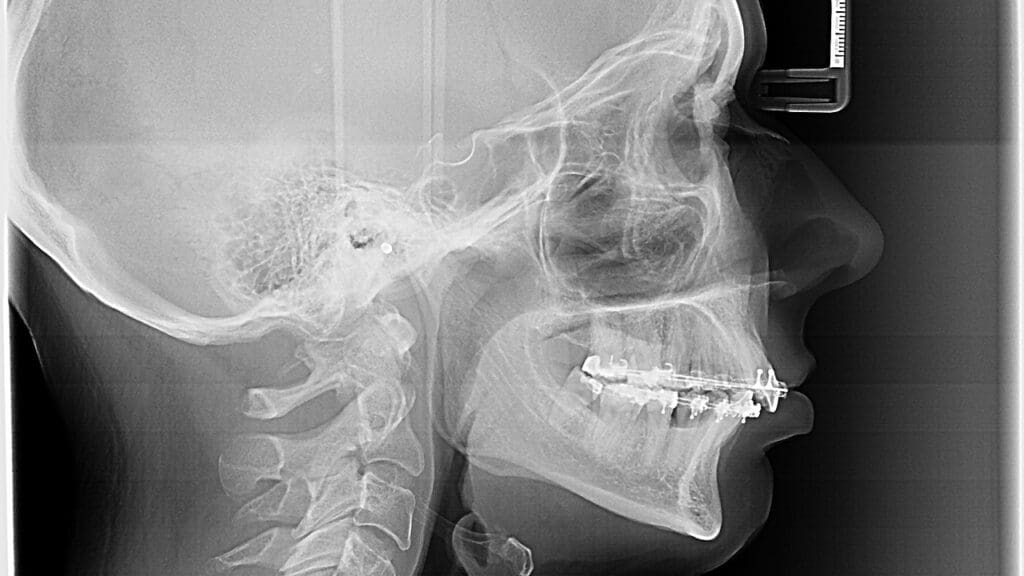

Diagnostic Tests and Imaging Studies

Diagnostic tests and imaging studies are vital for checking the cervical spine’s condition. We use X-rays, MRI scans, and CT scans to look at the spine’s structure and find any issues. These tests help us understand how severe the condition is and guide our surgical plan.

| X-rays | Assess bone structure and alignment |

| MRI Scans | Evaluate soft tissue and nerve compression |

| CT Scans | Provide detailed images of bone structure |